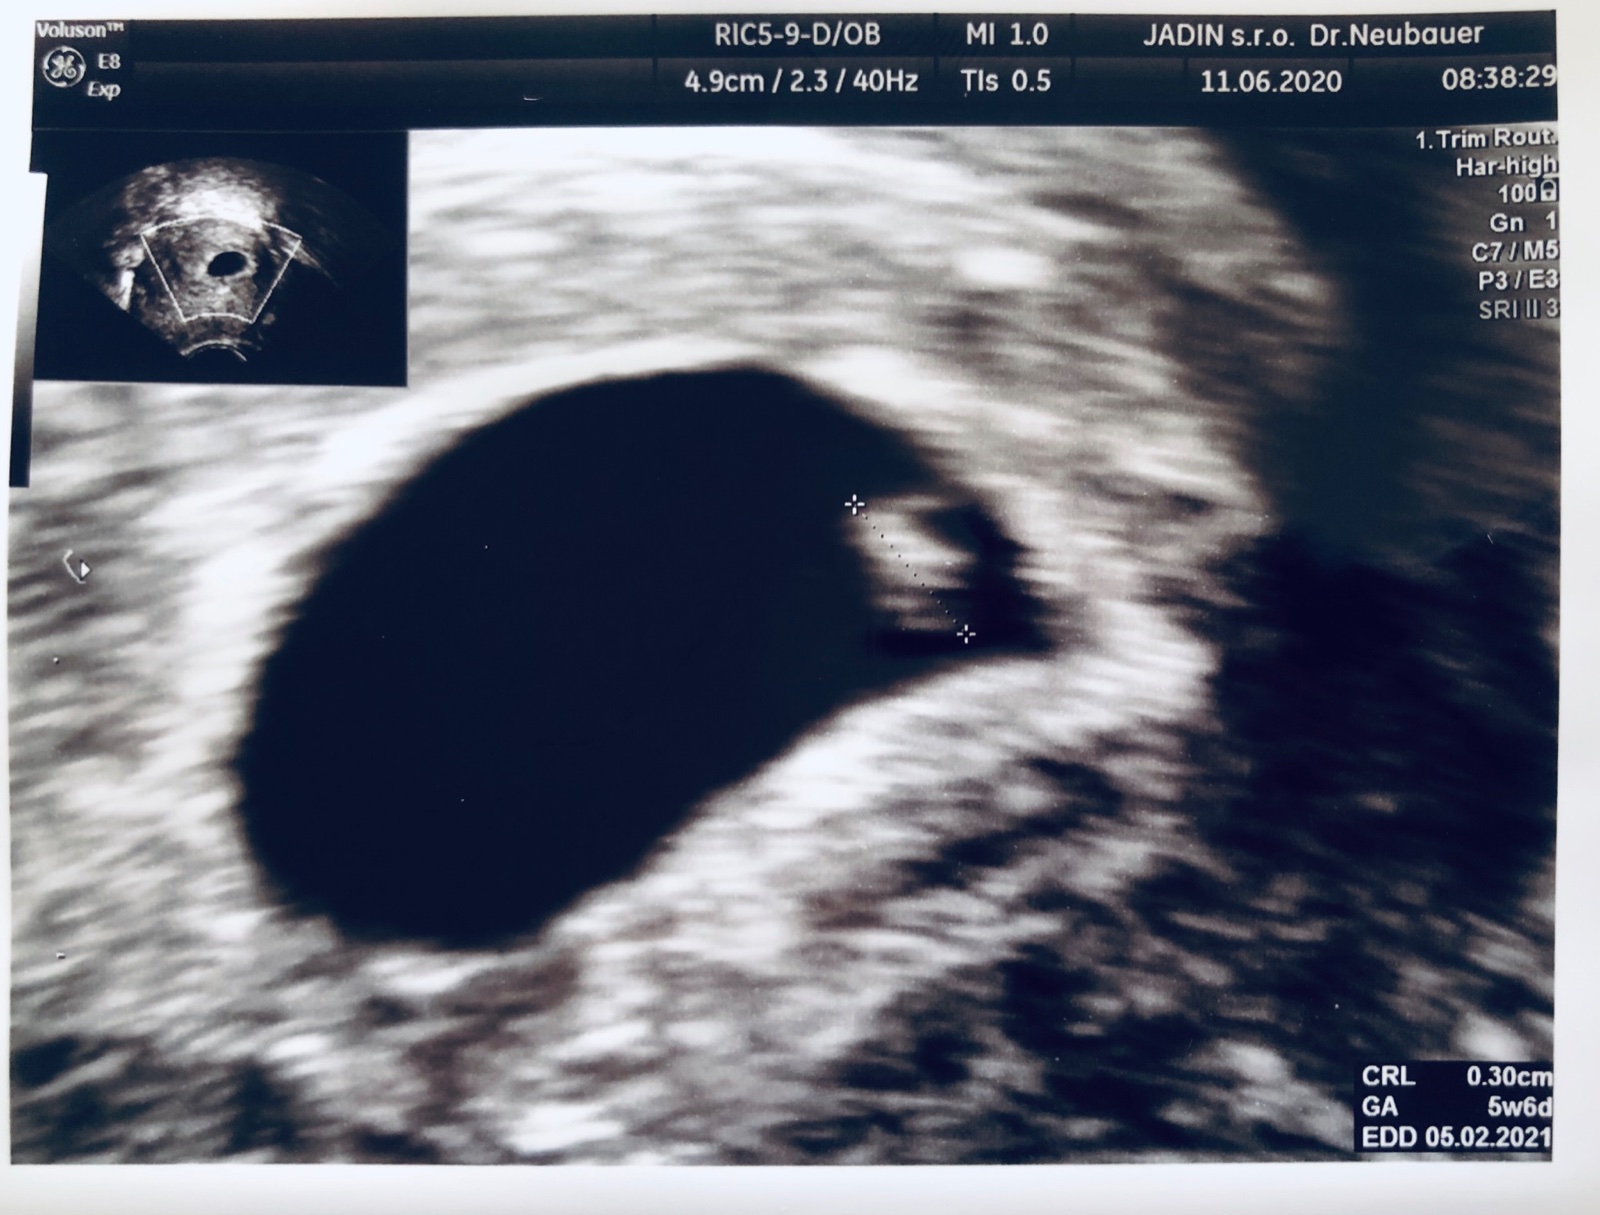

@mirka135 ahoj, tak 12dpo hcg 237, idem ešte zajtra to je 14dpo tak som zvedavá či to bude rásť ale podľa tabuľky je to asi v poriadku hodnota....na ultrazvuku nebolo ešte nič vidno